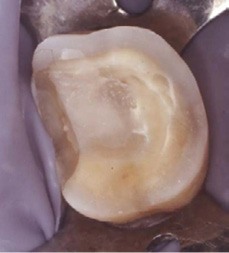

At the time of the examination, 10 (90.9%) ECs were in function in 10 patients. One EC had been lost after 12 years and 9 months due to periodontal disease in tooth #26. No restoration had loosened. Neither secondary caries nor radiographic failures were observed in the 10 PETT in function (Figs. 1a,1d; 2c; 3c,3d; 4c).

Fig. 1c EC after 9 years (Gradia, GC Corp., Japan)), (SC = Ex).

Fig. 4b EC after 10 years (IPS-Empress) (SC = Ex).

Meanwhile, dual and chemical curing resin cements, performed better than light or self-etching curing resin cements, in laboratory and clinical research (38-44). Nevertheless, increasing the exposure time through different thickness of ceramic materials and using high power light-emitting diode (LED) curing units, recent laboratory studies have found a greater degree of conversion and after 24 hours, greater microhardness values in light and dual-polymerization resin cement (45, 46). Therefore, the clinical procedures and the types of cements used, could have influenced the good Clinical Success (90%), (Figs. 1c, 2b, 3b, 4b).